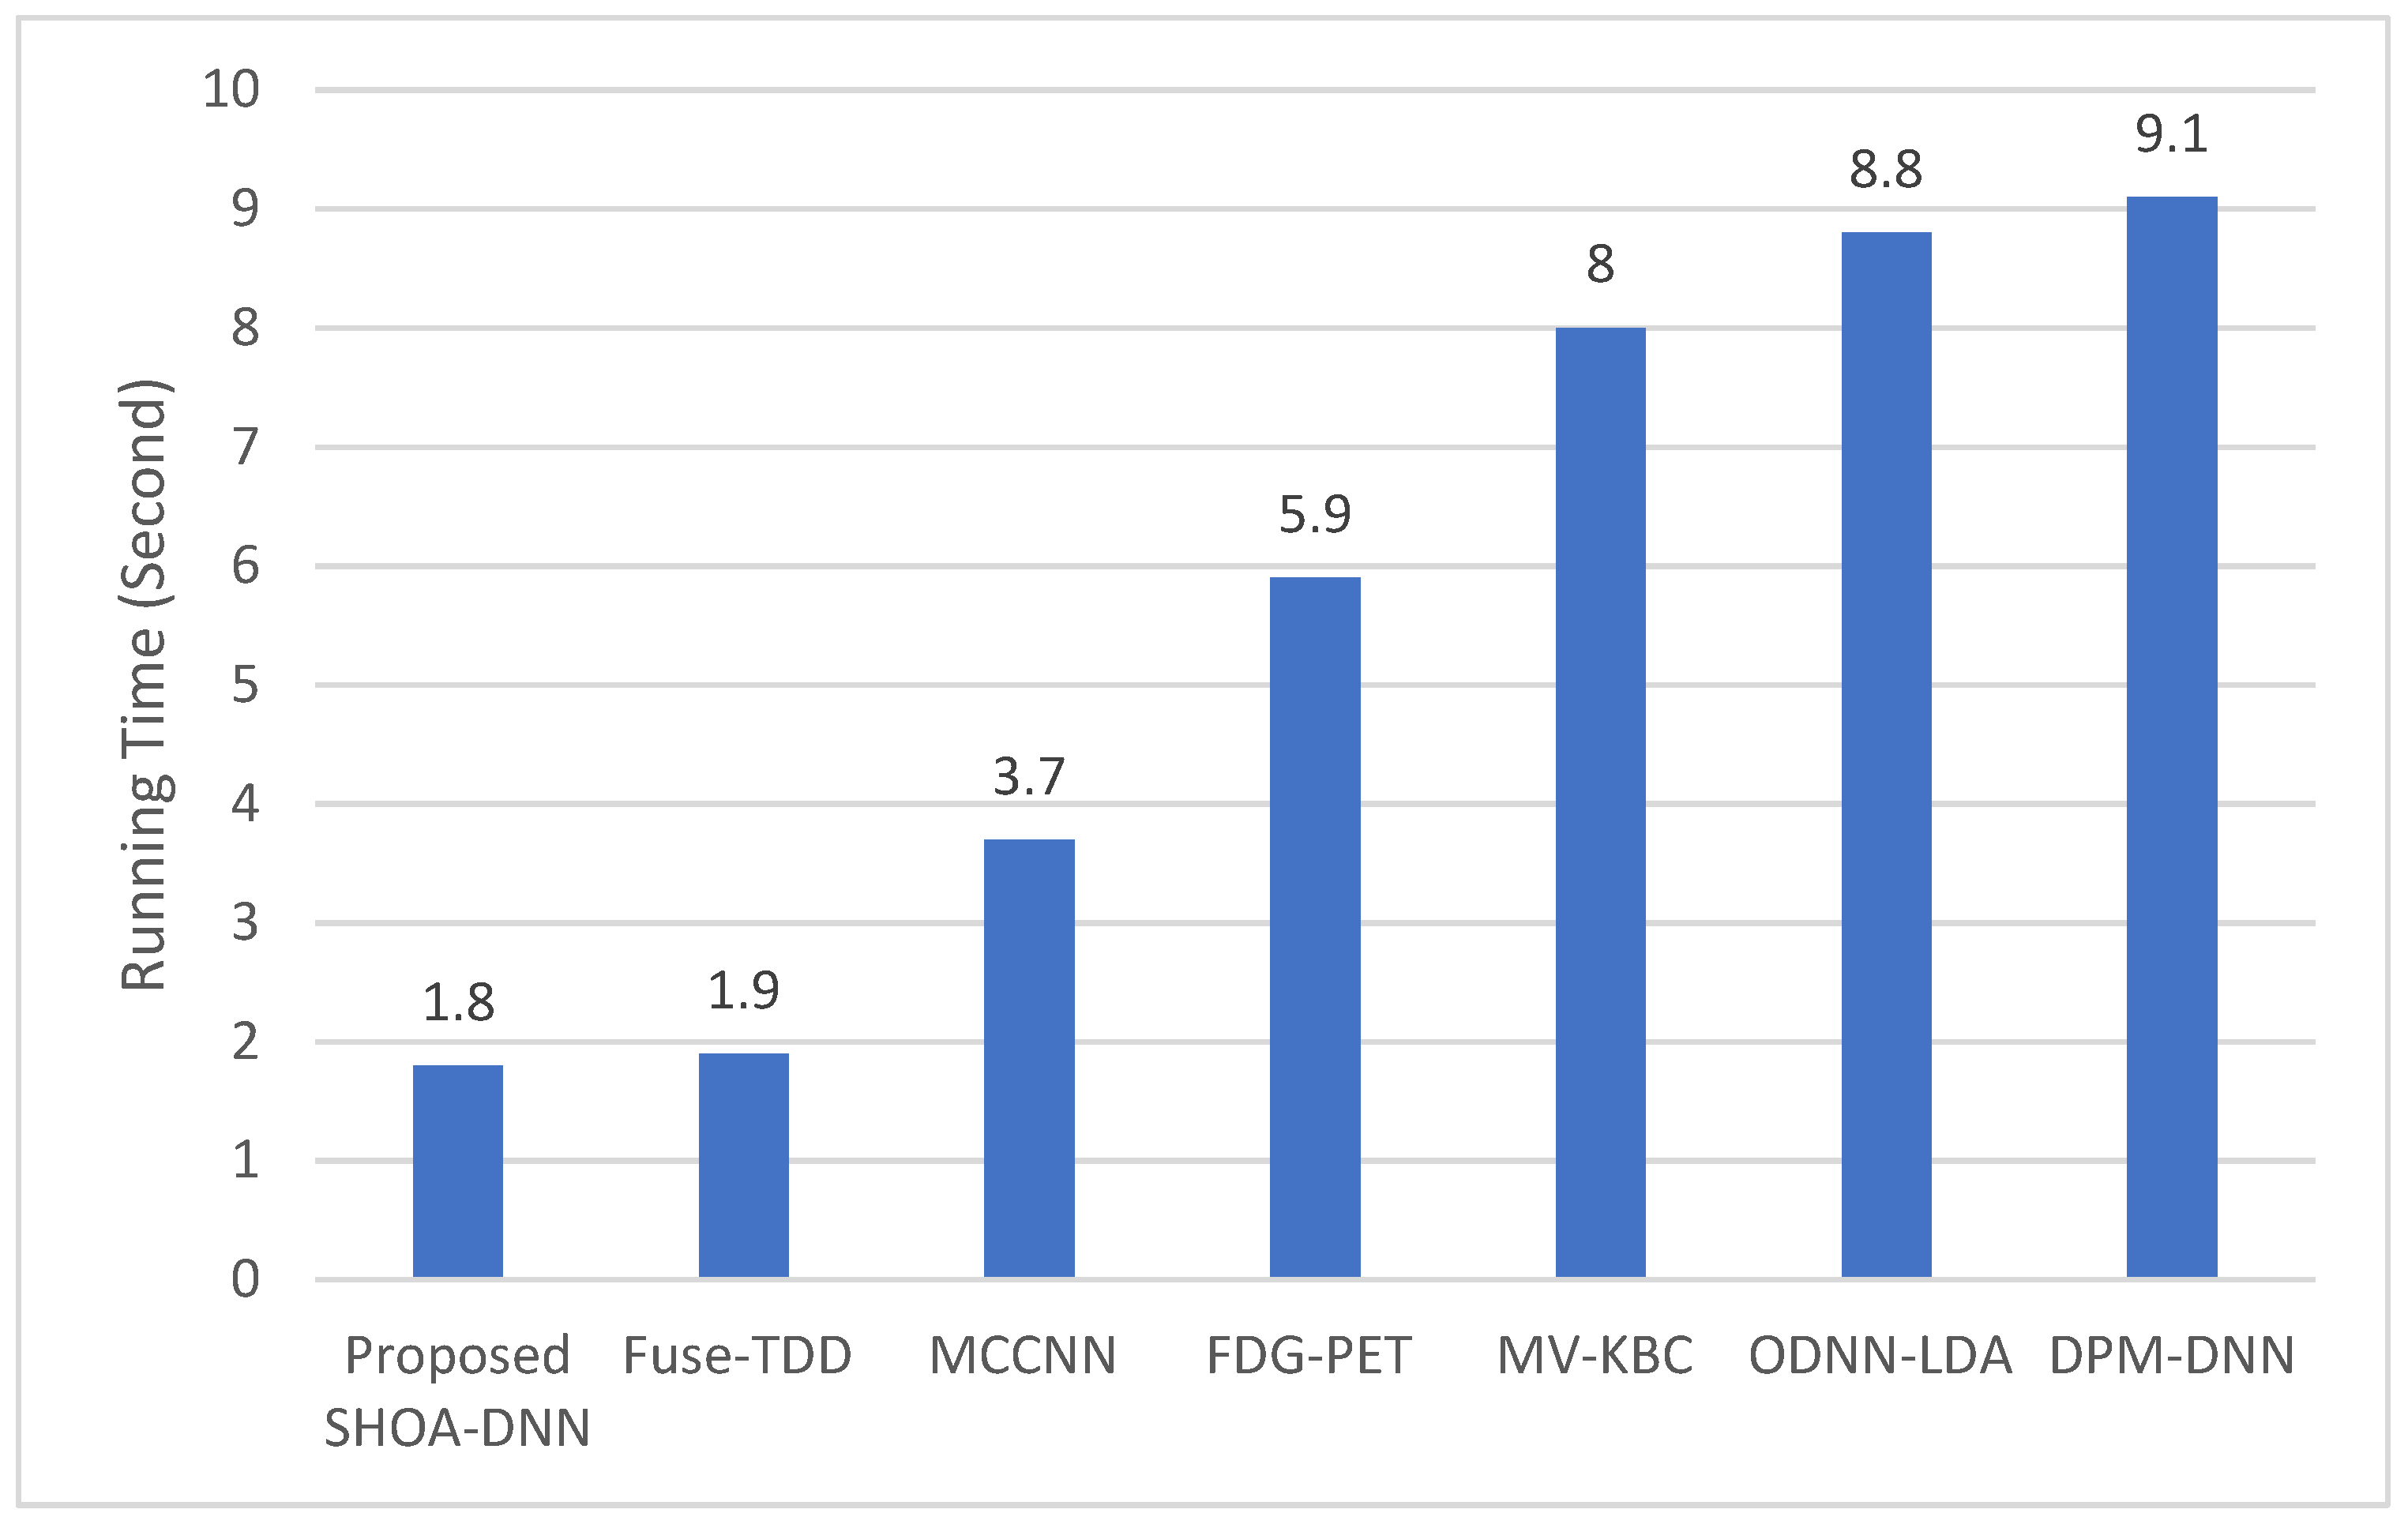

4.3. Performance Evaluation of the Proposed SHOA-DNN Using Training Time and Running Time

| Compared Schemes | Accuracy | Precision | Recall | Specificity | F-Score |

|---|---|---|---|---|---|

| Proposed SHOA-DNN Model | 99.13 | 98.84 | 98.64 | 99.32 | 98.72 |

| Fuse-TDD [18] | 89.53 | - | 84.19 | 92.02 | 89.00 |

| MCCNN [20] | 80.14 | - | 77.00 | 93.00 | 87.00 |

| FDG-PET [22] | 82.60 | - | 92.10 | 53.40 | 82.00 |

| MV-KBC [23] | 91.60 | 87.75 | 86.52 | 94.00 | 87.13 |

| ODNN-LDA [24] | 94.56 | - | 96.2 | 94.2 | 95.12 |

| DPM-DNN [26] | 93.60 | - | - | - | - |